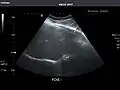

Spleen -